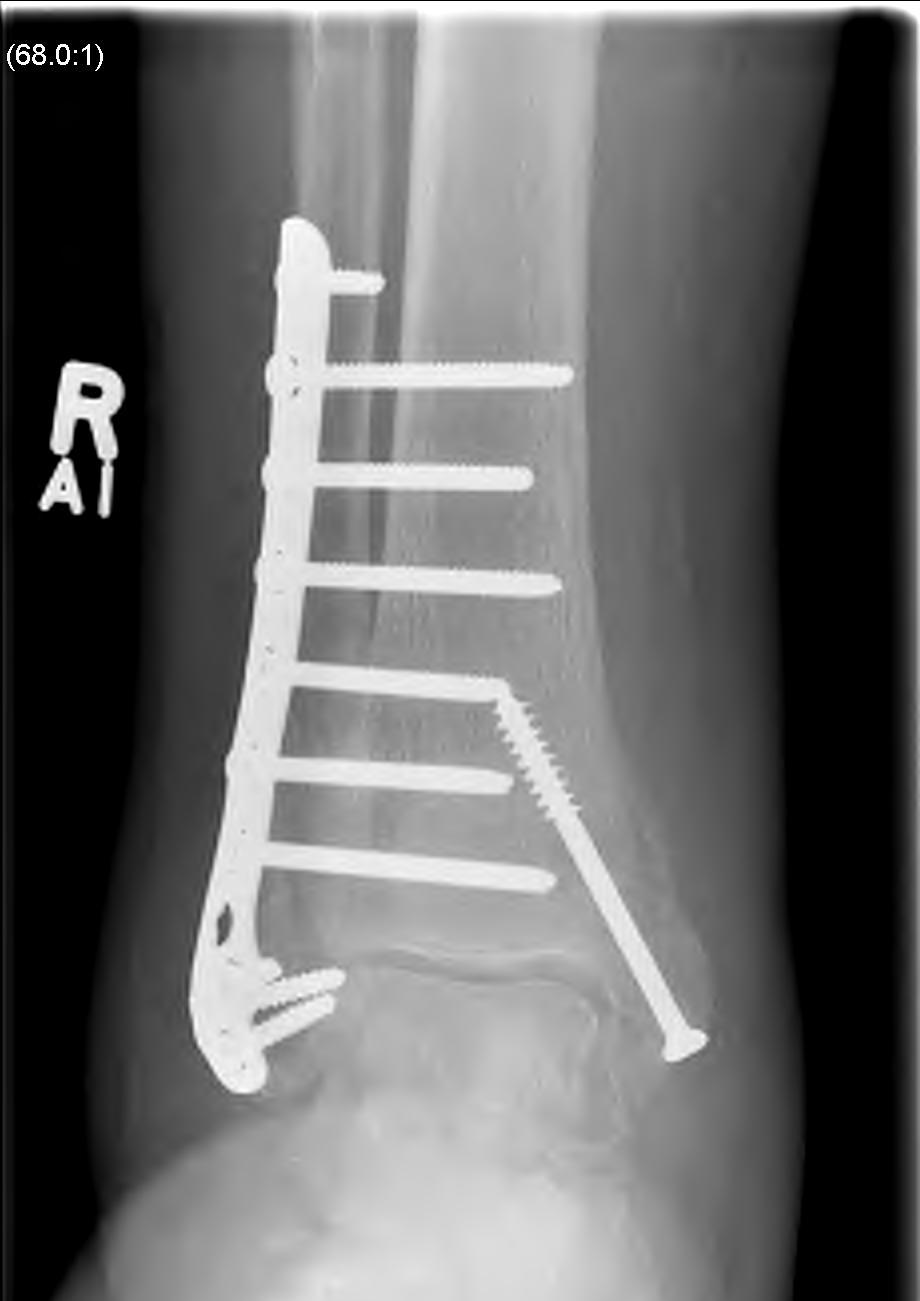

Operative Management

Diabetes / elderly / fragility fractures

Issues

High risk infection / wound complications / loss of fixation

Timing of surgery

Operate when swelling reduced / wrinkling / resolution of blisters

- risk not being able to close wounds / infection

- higher risk with bimalleolar / 2 incision operations